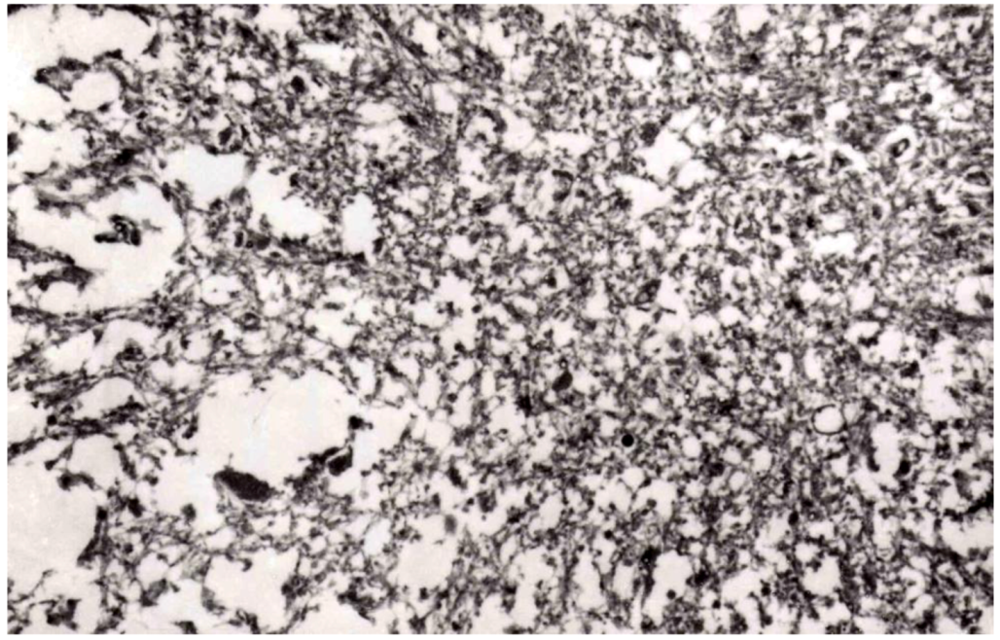

8. Neuropathology

- Beck, E.; Daniel, P.M. Kuru and Creutzfeldt-Jakob Disease: Neuropathological Lesions and Their Significance. In Slow Transmissible Diseases of the Nervous System; Prusiner, S.B., Hadlow, W.J., Eds.; Academic Press: New York, NY, USA, 1979; Volume 1, pp. 253–270. [Google Scholar]

- Beck, E.; Daniel, P.M.; Alpers, M.P.; Gajdusek, D.C.; Gibbs, C.J., Jr. Neuropathological Comparisons of Experimental Kuru in Chimpanzees with Human Kuru. With a Note on Its Relation to Scrapie and Spongiform Encephalopathy. Locarno, Switzerland, 31 May —3 June 1967; Burdzy, K., Kallos, P., Eds.; Additamentum to Arch Allergy and Appl Immunol: Basel, Karger, Switzerland, 1969; Volume 36, pp. 553–562. [Google Scholar]

- Beck, E.; Daniel, P.M.; Alpers, M.P.; Gajdusek, D.C.; Gibbs, C.J., Jr. Experimental kuru in chimpanzees. A pathological report. Lancet 1966, 2, 1056–1059. [Google Scholar] [CrossRef]

- Beck, E.; Daniel, P.M.; Asher, M.P.; Gajdusek, D.C.; Gibbs, C.J., Jr. Experimental kuru in chimpanzees. A neuropathological study. Brain 1973, 96, 441–462. [Google Scholar] [CrossRef]

- Beck, E.; Daniel, P.M.; Gajdusek, D.C. A Comparison between the Neuropathological Changes in Kuru and Scrapie, System Degeneration. In Proceedings of the VIth International Congress Neuropathological, Zurich, Switzerland, 31 August – 3 September 1965; pp. 213–218.

- Beck, E.; Daniel, P.M. Kuru and Scrapie Compared: Are They Examples of System Degeneration? In Slow, Latent, and Temperate Virus Infections; Gajdusek, D.C., Gibbs, C.J., Jr., Alpers, M.P., Eds.; US Dept Health, Education, Welfare: Washington, DC, USA, 1965; pp. 85–93. [Google Scholar]

- Beck, E.; Bak, J.; Christ, J.F.; Gajdusek, D.C.; Gibbs, C.J., Jr.; Hassler, R. Experimental kuru in the Spider monkey. Histopathological and Ultrastructural studies of the brain during early stages of incubation. Brain 1975, 98, 595–612. [Google Scholar] [CrossRef]